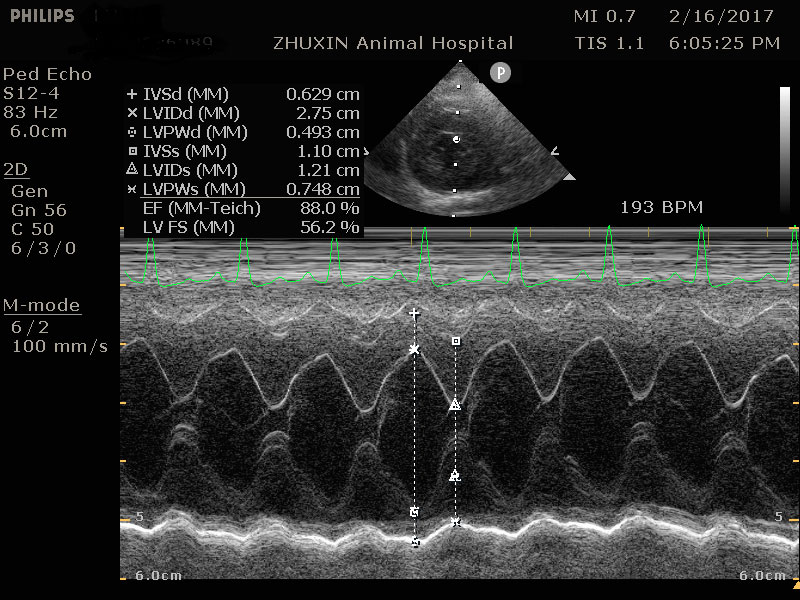

心臟快速掃描結果

嚴重的左心房擴張

左心室壁明顯肥厚

以下病例為10歲已絕育米克斯公貓,主人希望安排麻醉洗牙,術前健康檢查中發現貓咪已有嚴重心臟病,但主人平常並沒有發現任何異常。

及時發現心臟病,重新評估手術的必要性,調整麻醉及術後照護計畫可以避免事後的遺憾!